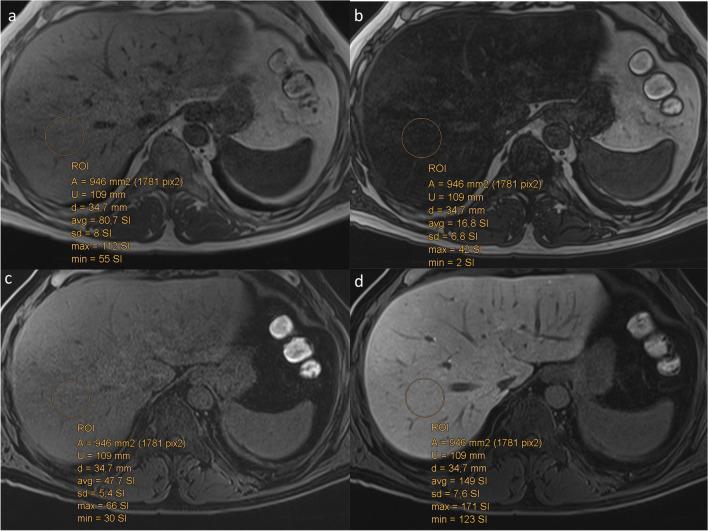

To compare unsupervised deep clustering (UDC) to fat fraction (FF) and relative liver enhancement (RLE) on Gd-EOB-DTPA-enhanced MRI to distinguish simple steatosis from non-alcoholic steatohepatitis (NASH), using histology as the gold standard.

A derivation group of 46 non-alcoholic fatty liver disease (NAFLD) patients underwent 3-T MRI. Histology assessed steatosis, inflammation, ballooning, and fibrosis. UDC was trained to group different texture patterns from MR data into 10 distinct clusters per sequence on unenhanced T1- and Gd-EOB-DTPA-enhanced T1-weighted hepatobiliary phase (T1-Gd-EOB-DTPA-HBP), then on T1 in- and opposed-phase images. RLE and FF were quantified on identical sequences. Differences of these parameters between NASH and simple steatosis were evaluated with χ- and t-tests, respectively. Linear regression and Random Forest classifier were performed to identify associations between histological NAFLD features, RLE, FF, and UDC patterns, and then determine predictors able to distinguish simple steatosis from NASH. ROC curves assessed diagnostic performance of UDC, RLE, and FF. Finally, we tested these parameters on 30 validation cohorts.

RESULTS

For the derivation group, UDC-derived features from unenhanced and T1-Gd-EOB-DTPA-HBP, plus from T1 in- and opposed-phase, distinguished NASH from simple steatosis (p ≤ 0.001 and p = 0.02, respectively) with 85% and 80% accuracy, respectively, while RLE and FF distinguished NASH from simple steatosis (p ≤ 0.001 and p = 0.004, respectively), with 83% and 78% accuracy, respectively. On multivariate regression analysis, RLE and FF correlated only with fibrosis (p = 0.040) and steatosis (p ≤ 0.001), respectively. Conversely, UDC features, using Random Forest classifier predictors, correlated with all histologic NAFLD components. The validation group confirmed these results for both approaches.